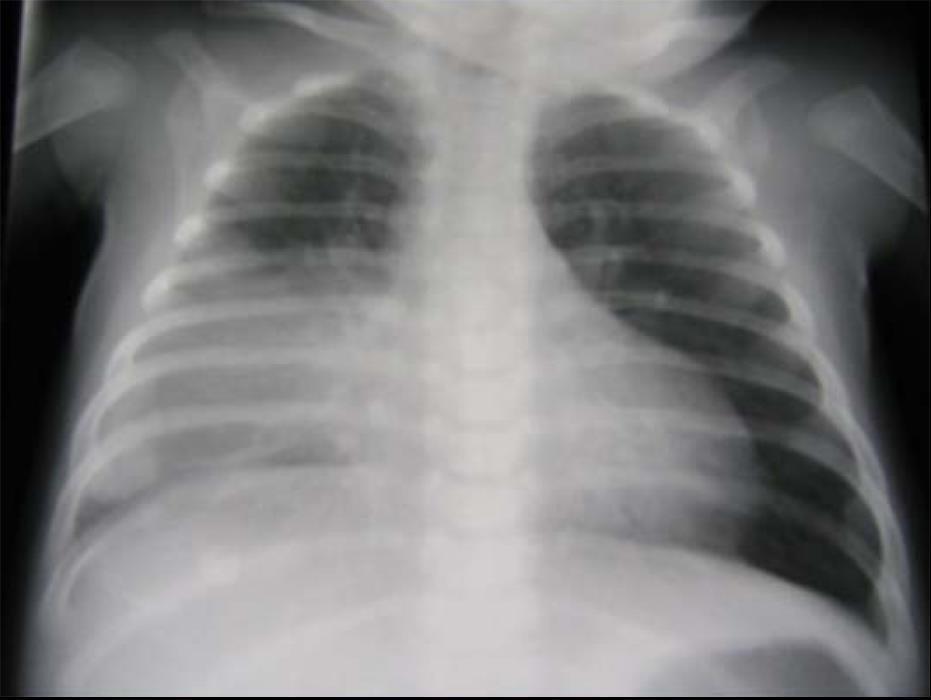

Vous entendez à l’auscultation des crépitants diffus sans foyer, un murmure vésiculaire bien perçu. L’abdomen est souple, il n’y a pas d’hépatomégalie ; les aires ganglionnaires sont libres. Les pouls fémoraux sont perçus. La fontanelle antérieure est normale, l’enfant est fatigué mais reste tonique. Il n’y a pas d’otite ni de purpura